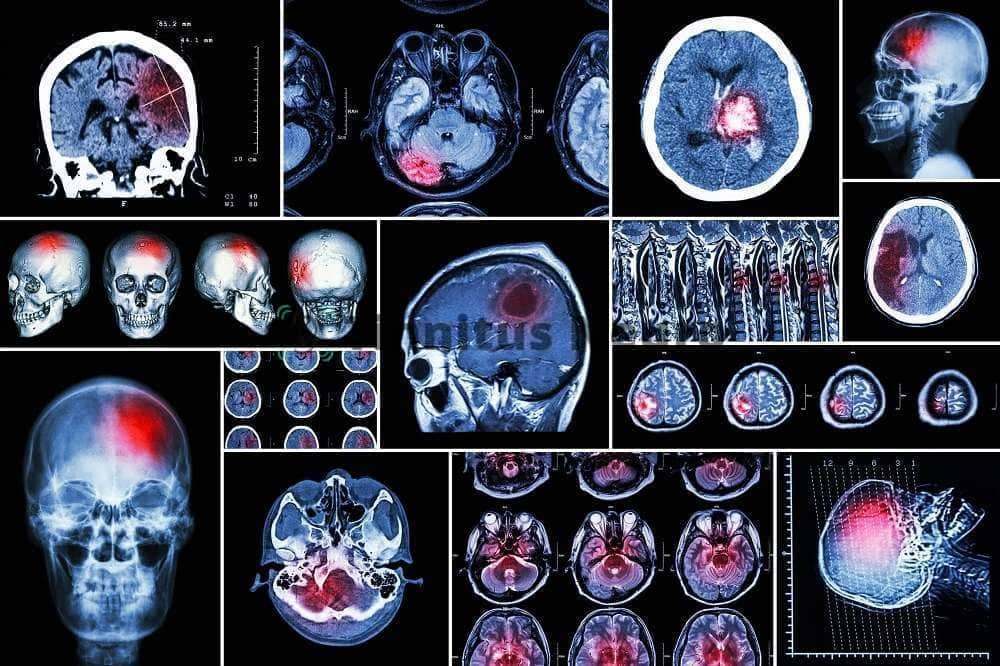

В клинке восстановительной неврологии установлен современный аппарат МРТ, с помощью которого можно получить идеальное изображение об особенностях структуры всего слухового анализатора, начиная от ушных косточек, заканчивая слуховой корой височных извилин.

При выяснении причин шума в ушах, методика МРТ незаменима. С ее помощью можно выявить многие проблемы, недоступные компьютерной томографии и другим методам исследования:

- Анатомические аномалии строения органа слуха (барабанной перепонки, косточек, улитки), черепа.

- Патологию ЛОР-органов, способную вызывать шум в ушах.

- Особенности кровообращения в сосудах позвоночника и собственно головного мозга.

- Стенозы и аневризмы артерий.

- Нарушения структуры центров мозга – увеличение или уменьшение размеров слуховых ядер, проводящих путей.

- Взаимоотношение между близкими анатомическими структурами центральной нервной системы.

- Опухолевые процессы.

- Начальные признаки атеросклероза.

- Проявления инсультов и инфарктов мозга.

- Очаги демиелинизации при рассеянном склерозе.

- Достоверные и неопровержимые признаки болезни Меньера.